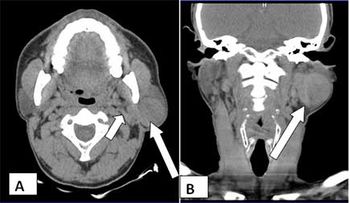

Case History: 35-year-old patient with gradually progressive, painless swelling in left parotid region, unremarkable history.